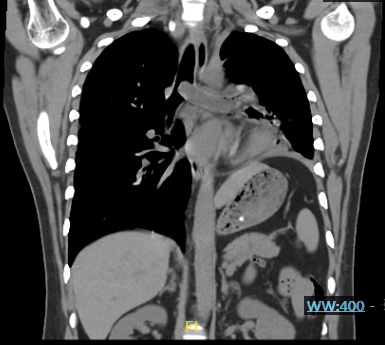

在呼吸科医生赶到前,急诊科接诊医生已为患者紧急完善了初步的化验检查并及时给予对症处理,刘亭威查看CT检查结果,提示患者主气管及左主支气管内可见条状实性病变,管腔严重狭窄,左肺周围见炎性病变。这些改变正是导致患者急性呼吸困难的原因。

CT可见肿物阻塞左主支气管(红框所示),并延伸至隆头上主气管处,阻塞部分右主支气管开口

刘亭威立即再经电圈套器套切,新生物基本切除,可见新生物残端位于左下叶基底段开口,以氩气刀喷灼残端,吸除左主支气管内溢出的大量分泌物,手术历时近1小时顺利结束,患者大气道梗阻得到充分缓解。

术后患者主气管及左主支气管阻塞完全开通,组织瓶内为切除的大量肿物组织